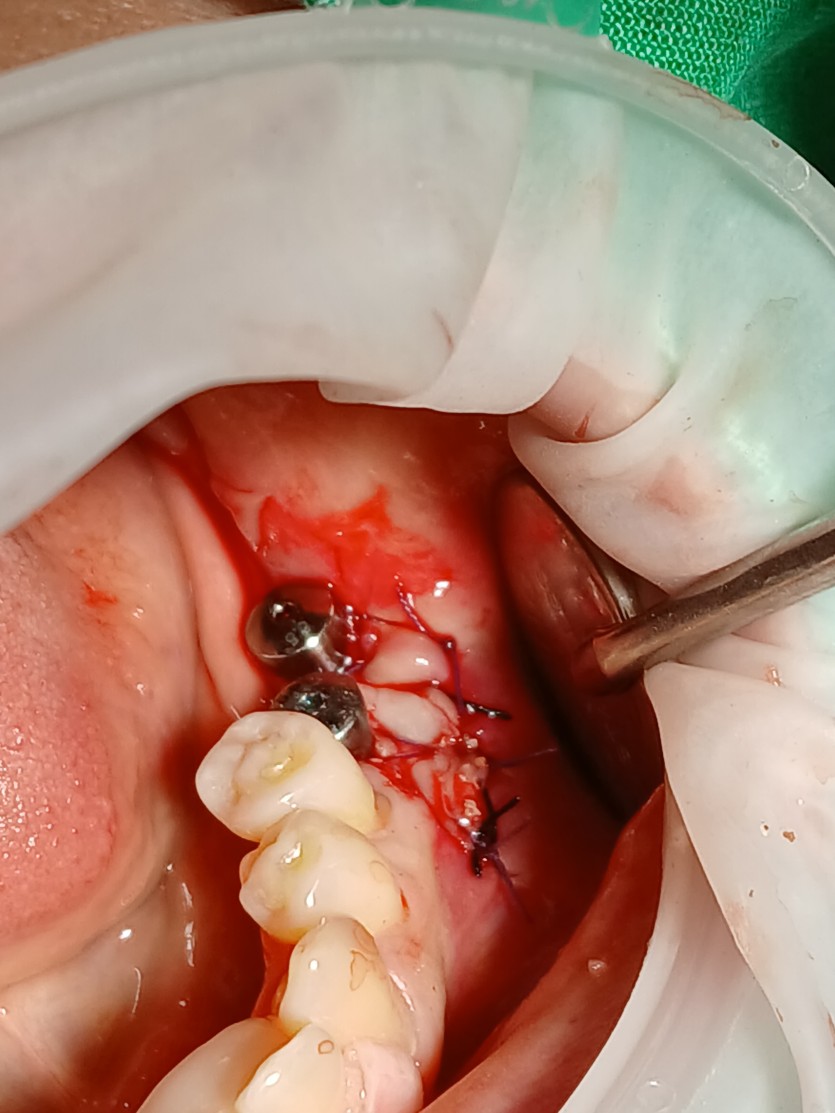

임플란트 잇몸이식 및 전정성형술

각화치은이 부족한 경우 잇몸이식을 통해

단단한 잇몸을 확보할 수 있습니다.

구강외과 전문의가 진료합니다.